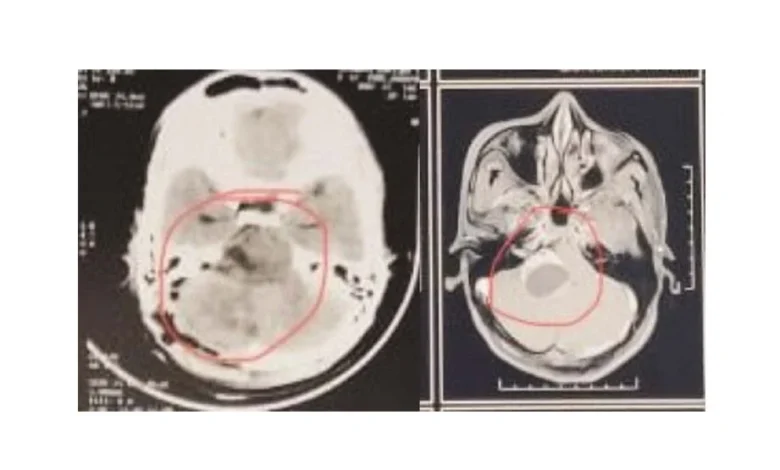

सदर रुग्णाला डाव्या हात व पायामध्ये कमजोरी, तीव्र वेदना, स्नायूंमध्ये आकडीपणा (स्पॅस्टिसिटी) तसेच रिफ्लेक्सेस वाढलेले असल्याच्या तक्रारी होत्या. एमआरआय तपासणीत मणक्याच्या मज्जारज्जूमध्ये (इंट्राड्यूरल) व मज्जारज्जूबाहेर (एक्स्ट्राड्यूरल) पसरलेली डम्बेल आकाराची गाठ आढळून आली. ही गाठ मज्जासंस्थेच्या आवरणातून बाहेर येऊन मणक्याच्या रक्तवाहिनीस (व्हर्टिब्रल आर्टरी) चिकटलेली होती. तज्ञ डॉक्टरांच्या पथकाने मणक्याची लॅमिनेक्टॉमी व आंशिक फेसिटेक्टॉमी करून गाठ पूर्णपणे काढून टाकण्यात यश मिळवले. शस्त्रक्रिया यशस्वीरीत्या पार पडली असून रुग्णाची प्रकृती सध्या स्थिर आहे. सदर रुग्णाच्या शस्त्रक्रियेचा खर्च शासनाच्या महात्मा जोतिबा फुले जीवनदायी योजनेच्या माध्यमातून मोफत करण्यात आला. या यशस्वी शस्त्रक्रियेसाठी न्यूरोसर्जन डॉ. अमोल ढगे यांचे मोलाचे सहकार्य लाभले. तसेच शस्त्रक्रिये दरम्यान उत्कृष्ट भूल व्यवस्थापनासाठी रुग्णालयाच्या भूलतज्ञ विभाग प्रमुख डॉ.विजया पाटील व चमुचे सहकार्य लाभले आहे. तसेच रुग्णाची प्रकृती स्थिर ठेवण्यासाठी व शस्त्रक्रियेचे काटेकोर व्यवस्थापनासाठी रुग्णालयाच्या बधिरीकरण विभाग, परिचारिका व कर्मचारी यांचे महत्वपूर्ण योगदान लाभत आहे. पीडीएमएमसी येथील तज्ञ वैद्यकीय डॉक्टरांच्या उत्कृष्ट कौशल्याने अत्यंत आव्हानात्मक असलेली शस्त्रक्रिया परस्पर समन्वयाने व प्रगत उपचार पद्धतीच्या सहाय्याने यशस्वीरित्या पार पाडल्याबद्दल श्री शिवाजी शिक्षण संस्थेचे अध्यक्ष श्री. हर्षवर्धनजी देशमुख, संस्थेचे पदाधिकारी व अधिष्ठाता डॉ. अनिल देशमुख, वैद्यकीय अधीक्षक डॉ पवन टेकाडे यांनी तज्ञ चमूचे अभिनंदन केले आहे.